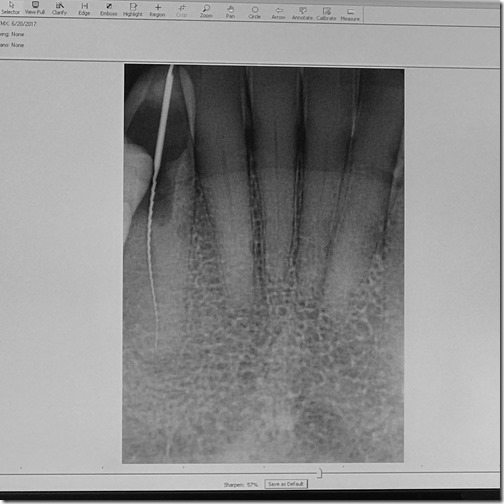

His assistant kept adding dilator to the area in order to open things up but it yielded no results with all the excavating. That’s where we hit a snag. The nerve was dead and there was no clear indication of when they would reach it. As a result, he had to keep taking x-rays in order to determine how much closer he was.

Now if you’ve never had a root canal done I won’t bore you (see what I did there?) with the details. I’ll just let this picture sum it up.

Success! And digital x-rays freaking rock. If you’re old enough to remember when x-rays had to be developed in a darkroom, you know what I mean.